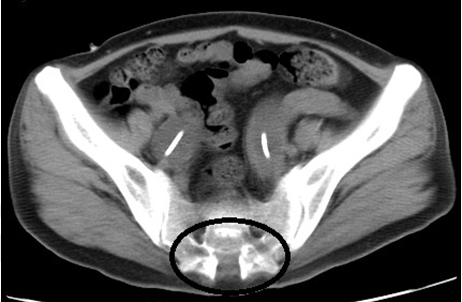

A 34-year-old female came to our hospital with complaints of anorexia and malaise that had persisted for approximately 10 days. She did not have abdominal or back tenderness, and her skin was dry. Her systolic blood pressure was 76 mmHg, and laboratory tests revealed an elevated creatinine level of 6.41 mg/dl, potassium level of 8.4 mEq/l, white blood cell count of 28,000/µl and C-reactive protein level of 17.98 mg/dl. She was admitted with diagnoses of urinary tract infection, acute kidney injury and hyperkalemia. At birth, she was diagnosed of schistorrhachis (Figure 1), and therefore, self-catheterization was performed. Abdominal computed tomography scan showed bilateral megaureters and hydronephrosis (Figure 2). Cystoscopy showed ends of both the ureters opening into the bladder. As her blood tests were abnormal (pH 7.360, serum HCO3 11.4 mmol/l), we performed hemodialysis once. Moreover, double J stents were placed in the ureters and antibiotic prophylaxis was administered. After treatment, her symptoms improved and blood tests became normal, and she was discharged. Based on this history, we diagnosed her as a case of neuropathic bladder secondary to schistorrhachis. | ||||||

A dilated ureter is considered as a megaureter, and any diameter of the ureter >8 mm is considered abnormal. Although the occurrence of megaureter is common in children, it is rare in adults. Megaureter can be classified as reflux, obstructed, and nonreflux-nonobstructed [1]. The causes of megaureter development are ureteropelvic junction obstruction, ureterovesical junction obstruction, neuropathic bladder, vesicoureterical reflux, high fetal urine output, and increased compliance of the fetal ureter. The presence of a megaureter could be considered when the patient has a urinary tract infection or hematuria. Moreover, ultrasonography scan, computed tomography, and magnetic resonance imaging scan can be used for its diagnosis. This was a case of reflux megaureter secondary to neuropathic bladder. Bilateral megaureters are rare in an adult. Medical treatment may include antibiotic prophylaxis for infection, anticholinergic medication, and clean intermittent catheterization for elevated detrusor leak point pressure. Surgical treatment may include ureteral plication or Infolding for moderately dilated ureters, and excisional tapering for massively dilated or thickened ureters. Treatment of secondary megaureter is conservative. However, treatment of primary megaureter may involve surgery or may be conservative [2]. | ||||||